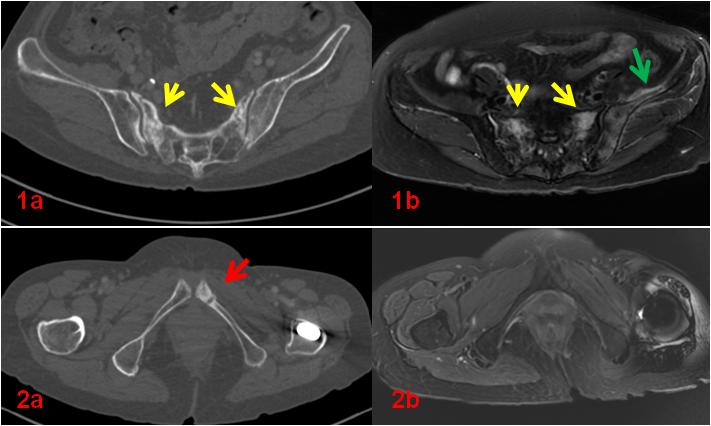

老年女性,1年前因直腸惡性腫瘤于外院行放射治療,此次常規(guī)復查平掃CT示骶骨及左側(cè)恥骨密度不均勻,左側(cè)恥骨骨質(zhì)斷裂;平掃MR示雙側(cè)骶骨翼、左側(cè)髂骨及左側(cè)恥骨異常信號(圖1、2);為進一步明確診斷行全身骨顯像ECT檢查(圖3)。

圖1、2初診CT、MR影像。CT示骶骨密度不均勻增高(1a,黃箭),同部位MR顯示壓脂信號增高(1b,黃箭),同時顯示左側(cè)髂骨及周圍軟組織壓脂信號增高(1b,綠箭);左側(cè)恥骨骨質(zhì)斷裂(2a,紅箭)。